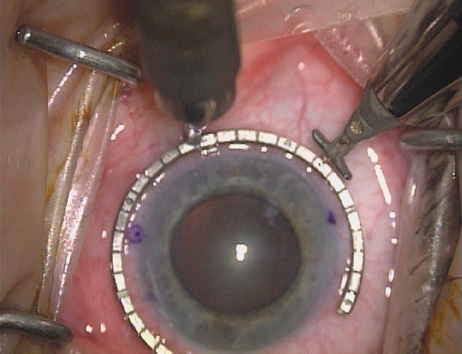

ways. Our preferred method makes use of a modified Fine-Thornton fixation

ring (Nichamin Fixation Ring and Gauge; Mastel Precision, Storz, Rhein

Medical). This instrument serves to fixate and position

the globe in order to optimize incision placement, as well as to delineate

the extent of arc to be incised. One visually extrapolates from

the limbus to marks on the surface of the ring. Each incremental mark

is 10 degrees apart, and bold hash marks (180 degrees) opposite

to each other serve to align and center the incision over the steep

meridian. This approach obviates the need to ink and physically mark

the cornea. If one desires, particularly when first gaining experience

with LRIs, a two-cut RK marker may be used to place ink marks upon the

cornea to show the exact extent of arc that is to be incised, in conjunction

with the fixation ring/gauge (Fig. 4). Alternatively, various press-on markers are available, such as

markers, rings, and blades for performing LRIs.  Fig. 4. The Nichamin Fixation Ring and Gauge serves to both fixate the globe and

delineate the extent of arc to be incised; a two-cut radial marker may

be used to mark the extent of arc to be incised, and the Mastel Nichamin

Force AK Diamond Blade with preset depth of 600 microns. Fig. 4. The Nichamin Fixation Ring and Gauge serves to both fixate the globe and

delineate the extent of arc to be incised; a two-cut radial marker may

be used to mark the extent of arc to be incised, and the Mastel Nichamin

Force AK Diamond Blade with preset depth of 600 microns.